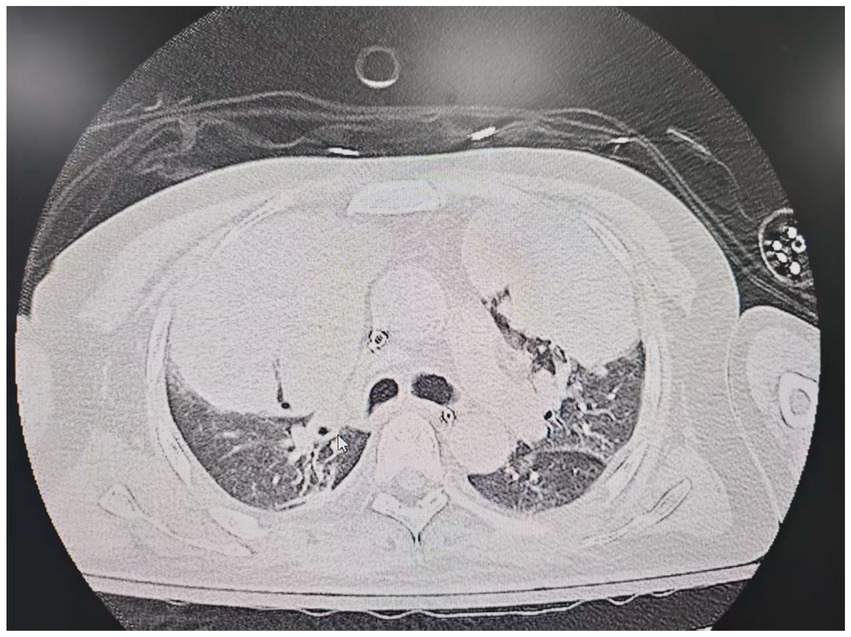

On the sixth day following VV-ECMO treatment, a favorable outcome was observed as the sputum culture yielded negative results (IL-6: 100 pg./mL, CRP: 195 mg/L), and there was a significant decrease in inflammatory indicators. The patient’s pulmonary condition demonstrated a marked improvement relative to the previous state, prompting a change in the antibiotic regimen to cefoperazone sodium-sulbactam sodium (2 g) administered every 8 h and voriconazole (200 mg) given via nasogastric feeding every 12 h. Concurrently, the patient’s oxygenation index improved, and lung function gradually recovered. This was based on the patient’s improved oxygenation and gradually recovering lung function, which indicated that the patient might be able to tolerate the discontinuation of ECMO support. The ECMO parameters were gradually titrated downwards, and the ECMO was weaned on the ninth day post-VV-ECMO treatment. At this point, the lung condition has improved significantly compared to before (Figure 2, and IL-6: 53 pg./mL, CRP: 202 mg/L). Given the patient’s persistent difficulty with extubation, the presence of retained respiratory secretions was suspected. Thus, percutaneous tracheotomy was performed on the second day post-ECMO weaning to alleviate the patient’s dyspnea symptoms. To further assess the patient’s lung condition following ECMO weaning, a repeat chest CT scan was performed on the fourth day after the procedure. The imaging revealed the emergence of new local masses with cavitation in the middle lobe of the right lung and the upper lobes of both lungs. This was suspected to be lipoid pneumonia with local lung tissue necrosis. Additionally, bilateral pleural effusion was noted, and the pneumonia had progressed compared with the previous state (Figure 3, and IL-6: 3557 pg./mL, CRP: 316 mg/L). Limited empyema was suspected, and the surgical department determined that the patient had indications for lung transplantation. However, the family members declined the surgery due to financial constraints. On the seventh day following ECMO weaning, the patient again exhibited hypotension, tachypnea, and tachycardia. Bedside chest X-ray suggested progression of exudation and consolidation in both lungs, along with bilateral pleural effusion (Figure 4, and IL-6: 5938 pg./mL, CRP: 322 mg/L). Septic shock secondary to pneumonia complicated by infection was suspected. Linezolid, at a dosage of 600 mg administered every 12 h, was added to the treatment regimen. Since the patient’s family members refused re-ECMO treatment, the deteriorating lung condition could not be reversed. On the ninth day post-ECMO weaning, the patient experienced cardiac arrest. Immediate bedside resuscitation was initiated. One minute later, the carotid artery pulsation ceased, and chest compression was terminated. The patient was declared clinically dead (The fluctuation of the patient’s oxygenation index can be observed in Figure 5, and the treatment route can be seen in Figure 6).

Figure 3

Figure 3. Lung CT scan on the fourth day after weaning from ECMO.